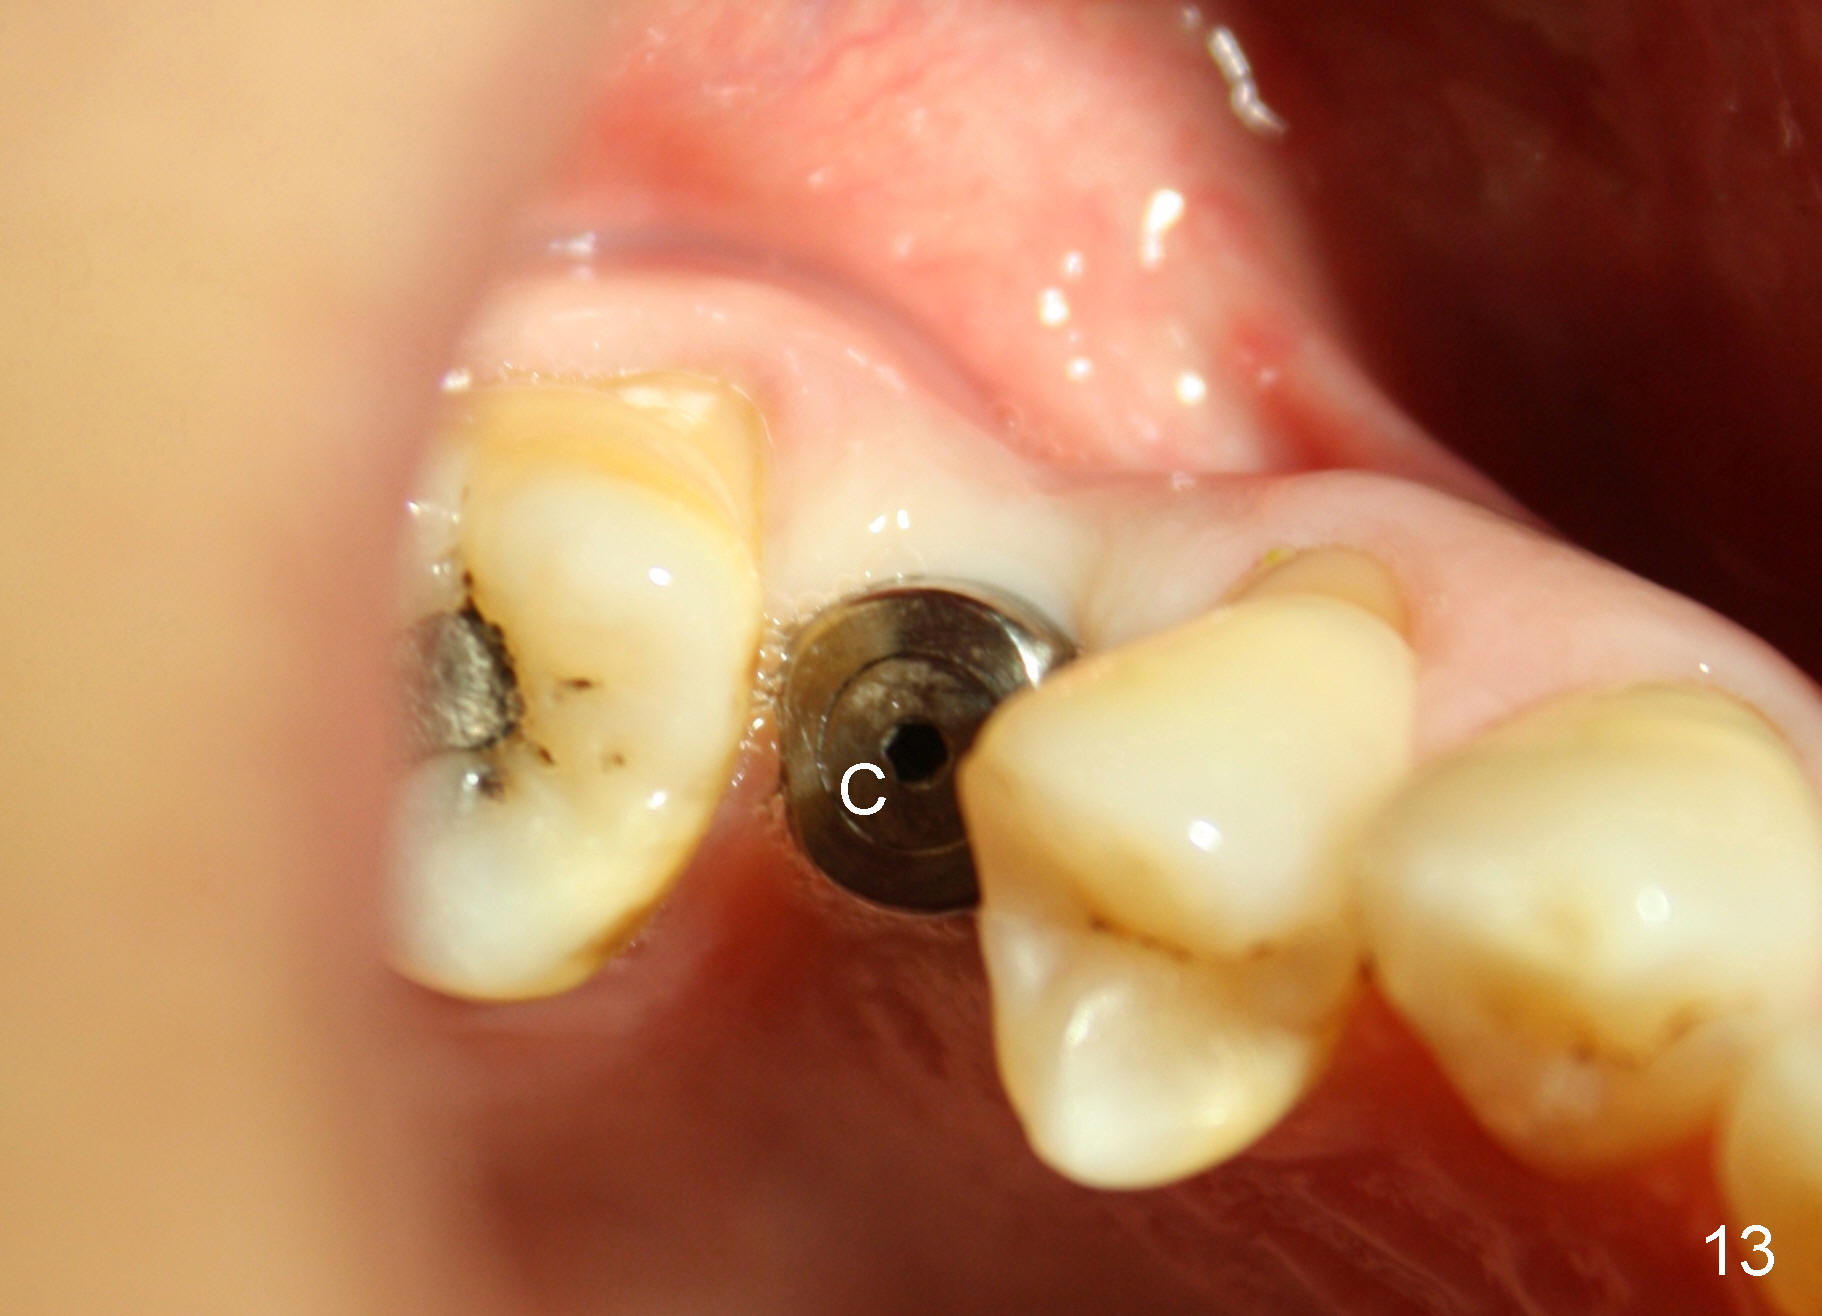

X-ray at 2.5 months postop shows crestal bone loss (Fig.12 *), although the implant is stable without inflammation (Fig.13 C: healing cuff). When the crown is bonded 3.5 months postop, there is no papilla (Fig.14 *).